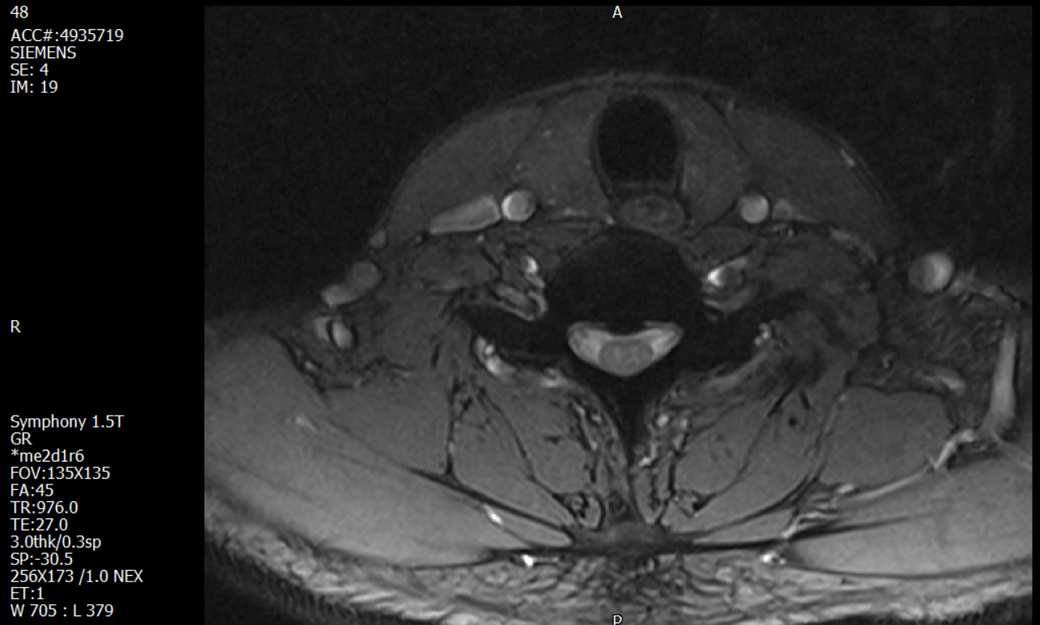

경추 요추 디스크 MRI판독 부탁드립니다.

- 3개월전 좌측 상지 저림(힘빠짐) 발생. 이틀뒤 에 좌측 하지 저림(힘빠짐) 발생.

(힘이 축처지는 느낌이라서 힘빠짐이라고 하지만, 실제 근력 문제, 감각이상, 활동 문제 없음)

-11월, 증상발생 직후 잠실소재 척추전문병원 MRI 요추경추 촬영 후 신경외과 박사 진료, 허리는 매우 건강, 경추는 퇴행성 진행되고 있지만 디스크라고 보기 어려움. 신경막만 살짝 건드리는 정도고 이 정도로 힘빠짐이나 저림이 오지 않고 원인은 다른 곳에 있을 가능성.

-12월, 분당서울대병원 재활의학과 진료, MRI 영상보고 딱히 다른 말은 없었음. 근전도 검사해보자 해서 신경전도, 근전도 검사 진행, 검사결과 이상없었고, 신경쪽 문제는 아예 배제해도 될것이라고 함. 정신쪽에 기인한 문제일 가능성 제시.

-올해 1월, 국립암센터 재활의학과 진료, 병명을 찾기가 쉽지 않을 것

-올해 1월, 분당서울대병원 신경과 진료, MRI영상보더니 디스크가 있고 저림과 힘빠짐이 이에 기인했을 가능성이 충분히 있다고함. (경추만 말한것인지 요추도 포함인지 모르겠으나 디스크 시술 방안을 제시함) , 팔다리가 우연이 동시에 저림이 올수 있는지에 대해서 물었더니 이틀 상간으로 발생했기 때문에 동시라고 보기 어렵다고함...

1. MRI 상 , 경추와 요추에 디스크가 있나요? 있다면 좌측 팔과 다리에 저림 및 힘빠짐을 줄 정도인가요?

• 1. MRI 사진을 보았을 때 디스크를 의심해볼 수 있는 소견이 살짝살짝 보이긴 합니다만, 상하지의 저림 및 힘빠짐을 유발할 정도인지는 솔직히 회의적입니다.

2. 영상의 퀄리티는 나쁘지 않아 보입니다. 굳이 재촬영을 하실 필요는 없어 보입니다.

3. 개인적으로는 디스크로 인한 증상이 아닐 것으로 보나, 만약 디스크가 맞다면 우연하게 목과 허리 디스크 발병이 이틀 간격을 두고 나타났을 가능성을 생각해야 하는데, 현실적으로 그 가능성이 높지 않습니다.

4. 말씀하신 것처럼 특히 요추부 MRI는 디스크를 찾기 어렵습니다.

상기 MRI 소견으로는 심한 증상을 보일 정도는 아니며 디스크의 가능성은 적어보입니다.